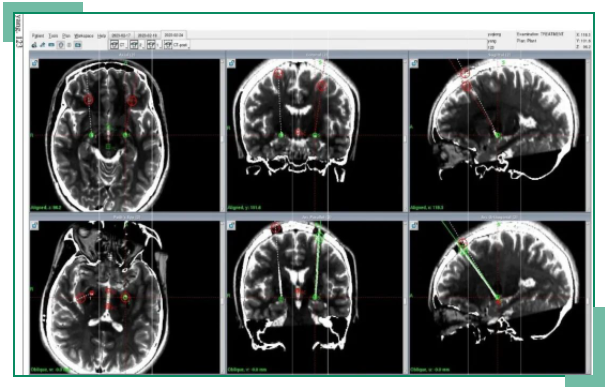

该例手术运用到高清晰3.0T核磁3D成像技术、64排CT薄层扫描及图像融合技术、MDT协作诊疗模式,以病人为中心,针对特定的疾病,以多学科团队为依托,制订规范化、个体化、连续性的综合治疗方案,确保最佳疗效。神经外科不但在现领域突破空白,还为广大帕金森病患者提供了又一更好的治疗方式。

脑深部刺激术(deep brain stimulation, DBS)是将电极植入到患者脑内,运用脉冲发生器刺激其大脑深部的某些神经核,纠正异常的大脑电环路,从而减轻神经功能障碍、减少药物治疗剂量。主要用于以帕金森病为代表的运动障碍性疾病,改善肌张力障碍等症状,提升患者生活质量。DBS手术与永久性的不可调节和不可逆的损伤大脑的一些治疗方法(烧灼或放疗)不同,DBS并不破坏大脑结构,可以允许今后的进一步治疗。